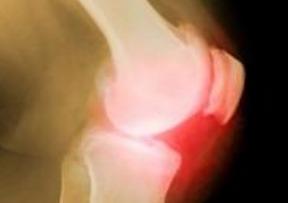

最近你的关节是不是有点不舒服啊?听说有人推荐说吃哈密瓜对骨关节炎有好处,你是不是也心动了呢?今天,我们就来好好探讨骨关节炎患者吃哈密瓜,到底是不是真的那么神奇呢?

那么,骨关节炎患者吃哈密瓜到底有没有好处呢?根据一些研究,哈密瓜中的营养成分对于缓解骨关节炎的症状可能有一定的帮助。

一些研究表明,维生素C和维生素A对于缓解关节疼痛有一定的效果。因此,适量食用哈密瓜,可能有助于减轻骨关节炎患者的关节疼痛。

哈密瓜中的维生素A和钾对于保护关节软骨有一定的作用。长期食用哈密瓜,可能有助于减缓关节软骨的退化。